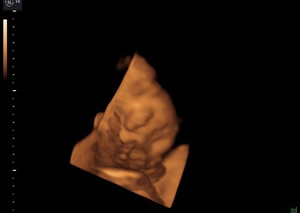

Ta nowa prezentacja (prezentacja 4D) pochodzi od dodania czwartego wymiaru jakim jest czas. Badanie płodu metodą 4D pozwala nie tylko na obrazowanie przestrzenne płodu ale również pozwala na obserwację ruchów twarzy, obserwację otwierania i zamykania oczu, ruchów języka, ssania palców. Przy korzystnym ułożeniu płodu, w odpowiednim wieku ciążowym ( najlepiej pomiędzy 15. a 35. tygodniem ciąży) możliwa jest diagnostyka szeregu wad rozwojowych płodu. Badanie 4D pozwala też na precyzyjne obrazowanie rozwoju płodu i umożliwia podejrzenie wyglądu dziecka, którego wygląd jest niemal identyczny z jego rzeczywistym wyglądem.

Zastosowanie techniki 3D i 4D ma szczególne zastosowanie w położnictwie. Umożliwiają precyzyjną ocenę narządów wewnętrznych płodu, np. serca, mózgowia, kręgosłupa, twarzy oraz w sposób istotny pozwalają na zwiększenie wykrywalności wad budowy płodu .